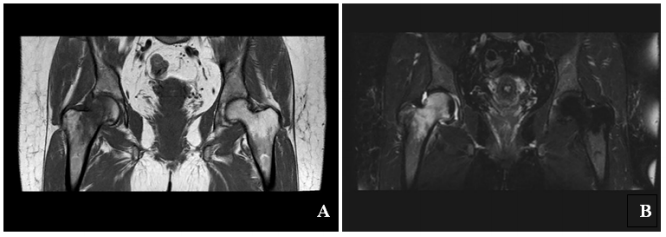

Conservative treatment is highly recommended, since TOH responds well. It includes; rest, preventing from weight-bearing, using walking aids, analgesic drugs and physiotherapy.3 In order to prevent contractures and muscle weakness, range of motion exercises and strengthening exercises (esp. abductor muscle) should be started as early as possible.9 The patient in this case report relieved with conservative treatment including rest, cane usage, NSAID and range of motion exercises. There are some reported cases in literature which are treated successfully by calcitonin10,11 bisphosphonates12–14 or teriparatide15 but further controlled studies are needed to support these findings (Figure 1).

Figure 1 1 MRI of the right hip.

A. T1 coronal- T1W coronal image shows extensive edema with signal hyperintensity in head and neck of right femur with concomitant joint effusion.

B. T2 spair coronal- Coronal T2 fat-saturated image shows extensive marrow edema in the femoral head and neck, mild edema in the medial acetabulum and

a small joint effusion.